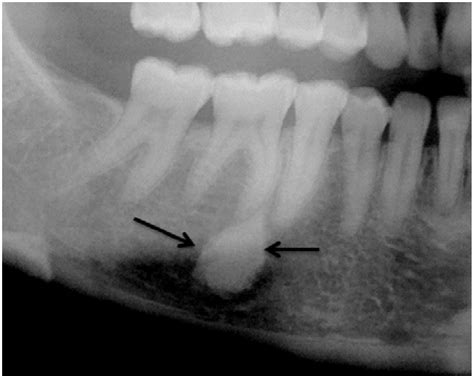

Bony lesions refer to any abnormal growths, defects, or changes in the bone tissue. These lesions can be benign (non-cancerous) or malignant (cancerous) and can occur in any part of the skeletal system. They are often detected through imaging techniques such as X-rays, CT scans, MRI, or bone scans. The characteristics of bony lesions can vary widely, making accurate diagnosis essential for appropriate treatment.

• Imaging Studies: X-rays, CT scans, MRI, and bone scans are commonly used to visualize the lesion and determine its characteristics.